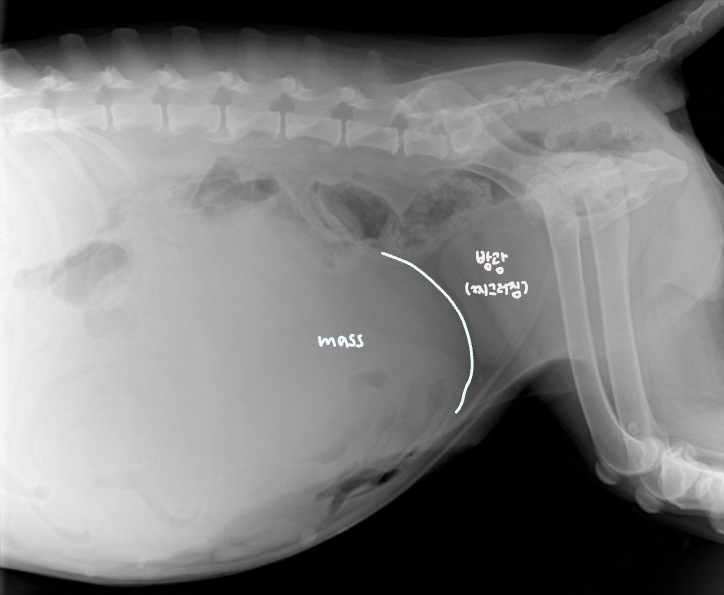

Fluid or Mass

- Fluid : ์ธ์ธก์์์ ์ค์์ผ๋ก ๋ชจ์. diffuseํ ์ฐ๋ถ์กฐ์ง ๋ฐ๋.

- Mass : ์๋ฆฌ๋ฅผ ์ฐจ์งํจ โ ์ฅ์ ๋ฐ์ด๋. & ์ข ์์ด ์ปค์ง๋ฉด์ ์ถํ์ ์ ๋ฐ.